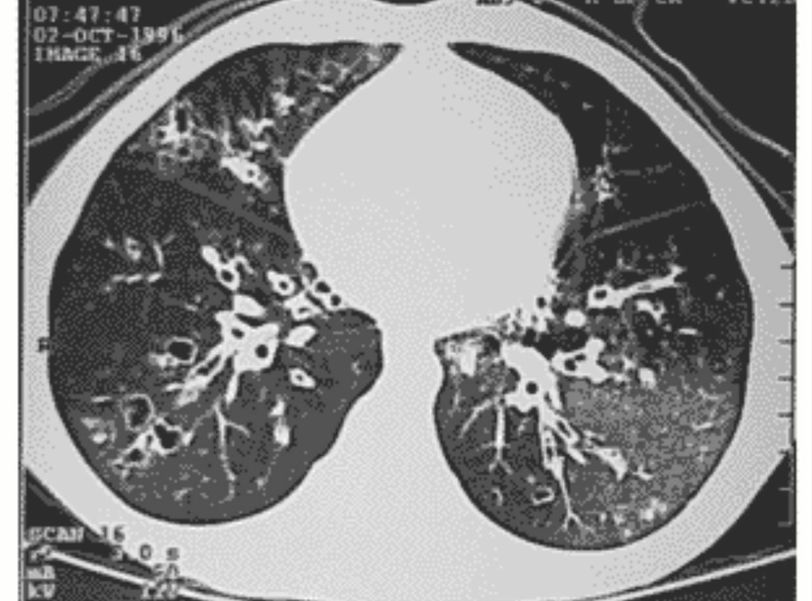

Bronchiolitis obliterans (popcorn lung) 🍿

🔹Symptoms more than 60 days lead to fibrosis of the airway 🔹Post adenovirus or lung transplant 🔹 Best diagnostic via open lung biopsy or transbronchial biopsy 🔹Can be seen in Chronic rejection post lung transplant

Hand in glove appearence